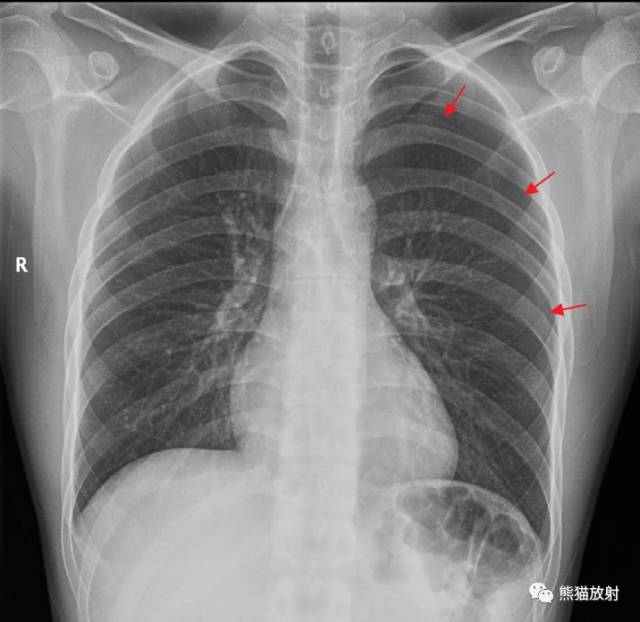

右侧气胸(肺被压缩约70%):

气带宽度略大于患侧胸廓的1/2 , 右肺明显受压 , 可见条片状高密度影 。